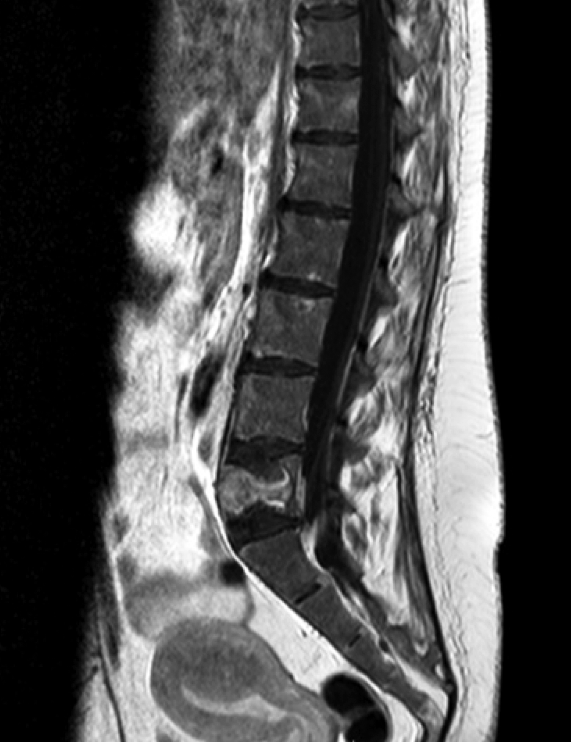

La TAC lumbosacra describía aumento difuso de la densidad ósea generalizada con múltiples lesiones osteolíticas en todos los cuerpos vertebrales, sacro, porción visible de ambos ilíacos y fractura patológica en L5. (Figura 1)